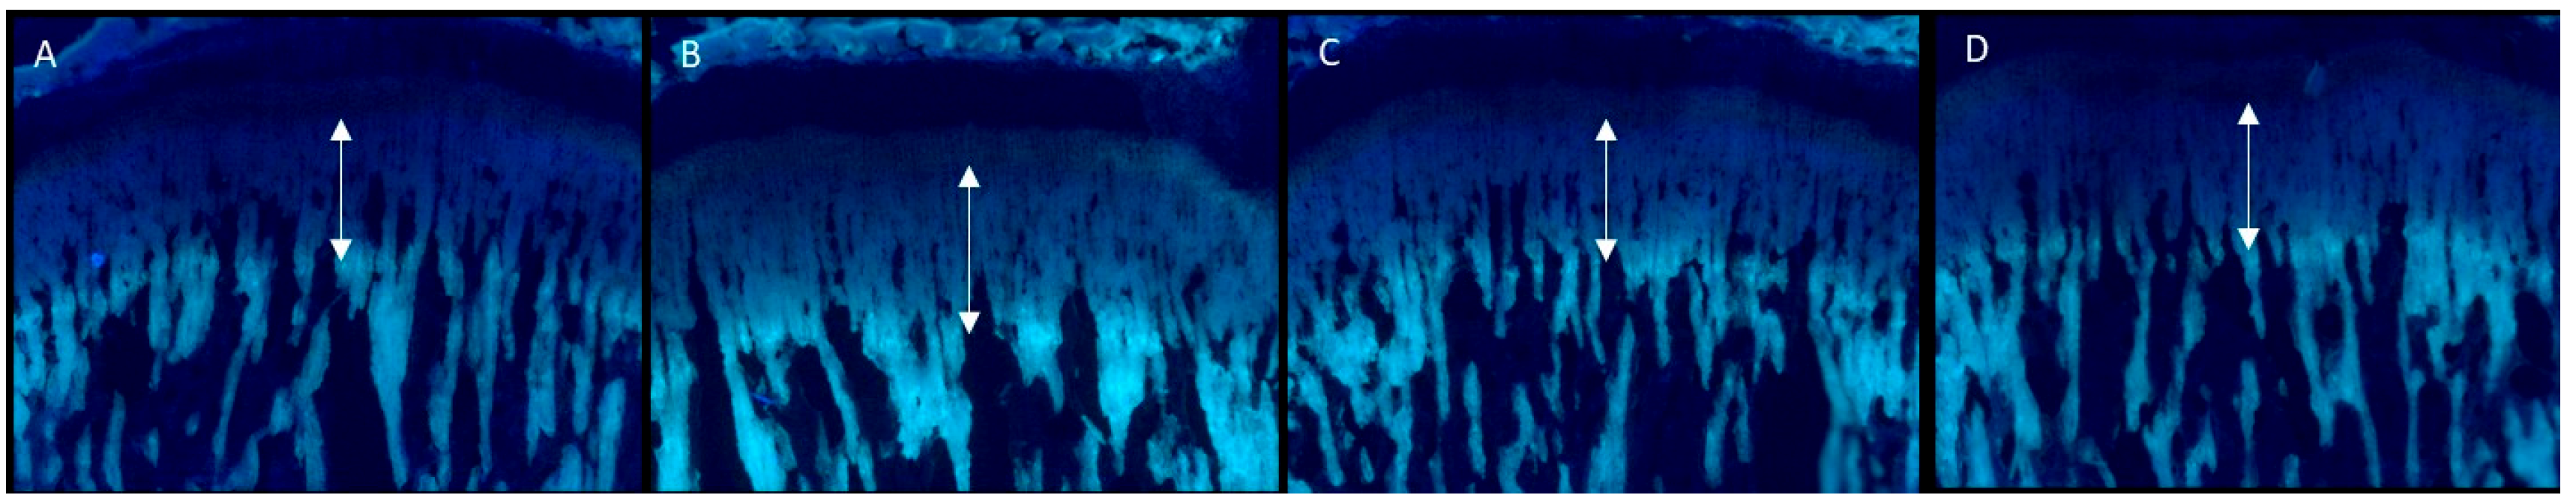

2.3. Effects on GP Height

| Control | rhGH 200 μg/kg (s.c.) | EEM 50 mg/kg (p.o.) | EEM 200 mg/kg (p.o.) | |

|---|---|---|---|---|

| overall height of GP (μm) | 350.3 ± 19.6 | 365.4 ± 17.3 *** | 368.2 ± 27.7 * | 368.0 ± 31.4 * |

| resting zone | 22.0 ± 5.3 | 21.4 ± 5.2 | 22.3 ± 5.8 | 21.1 ± 4.9 |

| proliferative zone | 119.9 ± 11.5 | 127.3 ± 15.7 ** | 132.0± 12.2 ** | 125.8 ± 12.8 |

| hypertrophic zone | 198.5 ± 12.7 | 203.3 ± 17.7 | 207.5 ± 22.1 | 208.7 ± 19.1 * |